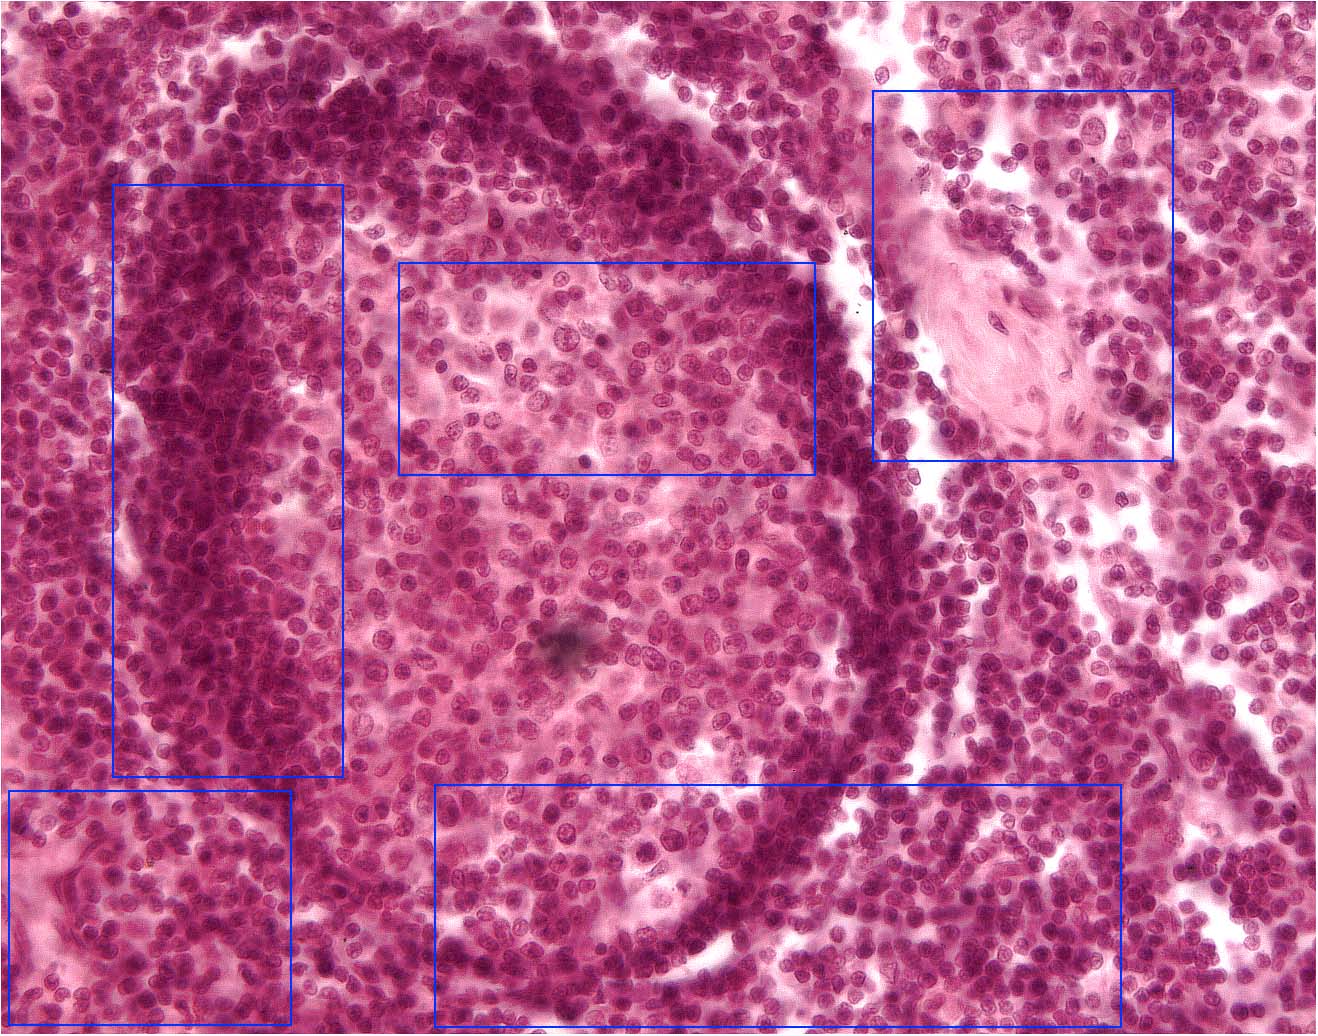

Return To Lowest Magnification

Immunology Main Page